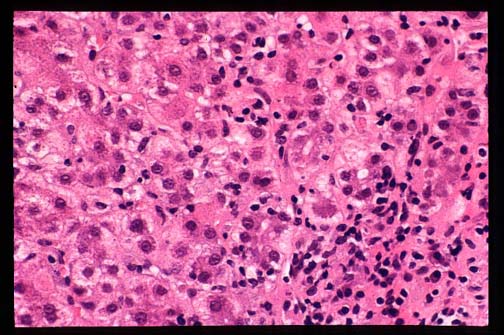

Fig. 9-1-1-Autoimmue

hepatitis.

A portal field with chronic inflammatory cells, mostly lymphocytes and plasma cells. In this hepatitis, contrary to viral hepatitis plsma c present in a significant number.

Fig. 9-1-2-Autoimmune hepatitis.

Periportal piecemeal necrosis with chronic

in inflammation, plasma cell reaction and

portal fibrosis.

The vulnerable area affected by autoimmune hepatitis is the periportal region. There is marked portal and periportal chronic inflammation with lymphocyte and macrophages which spill through the limiting plates encircling periportal hepatocytes,("rosetting") which are destroyed,("piecemeal necrosis")."Bile duct lesion"

Connective tissue replaces the lost parenchyma. The portal tract is expanded and assumes a"maple leaf"configuration. Periportal necrosis and fibrosis may extend far rom the portal region and link with an adjacent portal tract forming a bridging necrosis. Cirrhosis may follow. This process is similar to any other chronic active hepatitis. Only the presence of an excessive number of plasma cells and the rosetting phenomenon may indicate an autoimmune process, but their scarcity or absence do not rule out this condition. The histological form of lobular hepatitis especially in relapses is a distinguishing finding from viral hepatitis